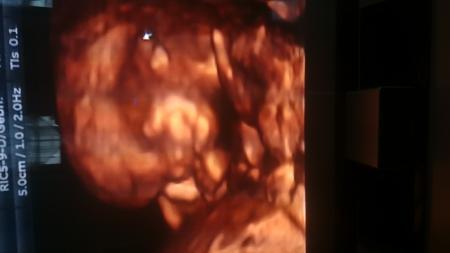

Es war so schön. Haben ein 3D Video von unserem Baby bekommen und haben die Nackenfaltenmessung machen lassen. Alles perfekt. Bin sogar eine Woche weiter und hab ein Beschäftigungsverbot bekommen

Danke ihr Lieben. Habe leider nur eine DVD bekommen aber habs mal abfotografiert. Baby ist 6,54 cm groß